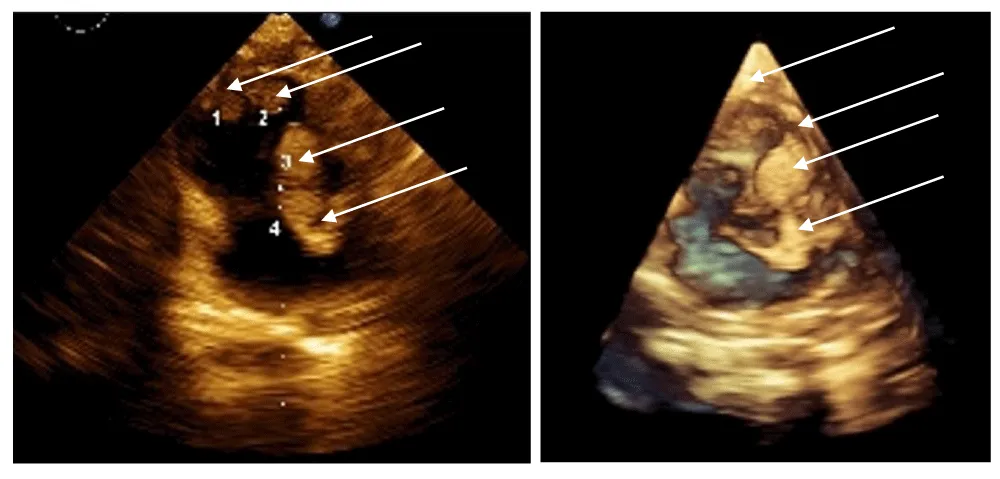

After initiation of treatment, regression was already observed by the end of the first month, both in density (echogenicity of the formations) and in size, cutting their sizes to around half (10-12mm). By the end of the third month, the lesions were almost completely resorbed—the intracavitary ones entirely—while data for hyperechogenic areas in the septum persist.

The best cardiac response (BCR) occurred between 4 and 6 months of therapy, with complete resolution of intracardiac tumors on echocardiography (Figure 2) [3].

Following initiation of therapy, an early treatment response was observed, with reduction in both lesion size and echogenicity evident by the end of the first month. By the third month of treatment, near-complete regression of the lesions was documented, with full resolution of the intracavitary masses and persistence only of limited hyperechogenic areas within the septum. While spontaneous resorption is noted in such cases, the time frame for such resorption to occur is normally far wider.

At the most recent clinical follow-up, after discontinuation of therapy, no recurrence or progression of cardiac lesions has been detected on echocardiographic evaluation. The patient remains clinically stable, with preserved cardiac function and normal hemodynamic status, supporting a sustained therapeutic response and favorable short-term outcome.